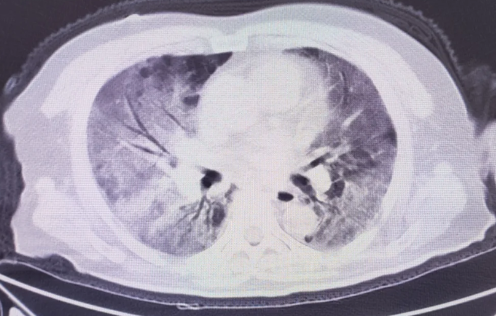

白肺是目前很多人比较担心的问题,因为肺部感染比较严重的话,可能会出现白肺的情况,而不少人不知道白肺到底是什么。那么,白肺症状表现有哪些?白肺治疗要多久能恢复?一起来看看趣丁网带来的详细介绍吧!

白肺症状表现有哪些

1、典型症状:本病最典型的症状是呼吸困难,如果是轻度白肺病,呼吸困难通常发生在剧烈活动时,因此常被忽视,或误诊为其他肺部疾病。随着病情发展,患者在静息状态下也可能出现呼吸困难。

2、其他症状:呼吸困难的患者还会伴有干咳、乏力等症状,有的患者还会出现指间杵状,有的患者还会出现全身不适、体重减轻和发热等症状。

3、并发症状:白肺疾病如果合并肺气肿,患者稍有活动就会出现气短、胸闷和气短症状。严重的情况下,在夜间睡眠时,血液的氧饱和度会显著降低,导致肺动脉增加,从而导致打鼾和呼吸暂停症状。